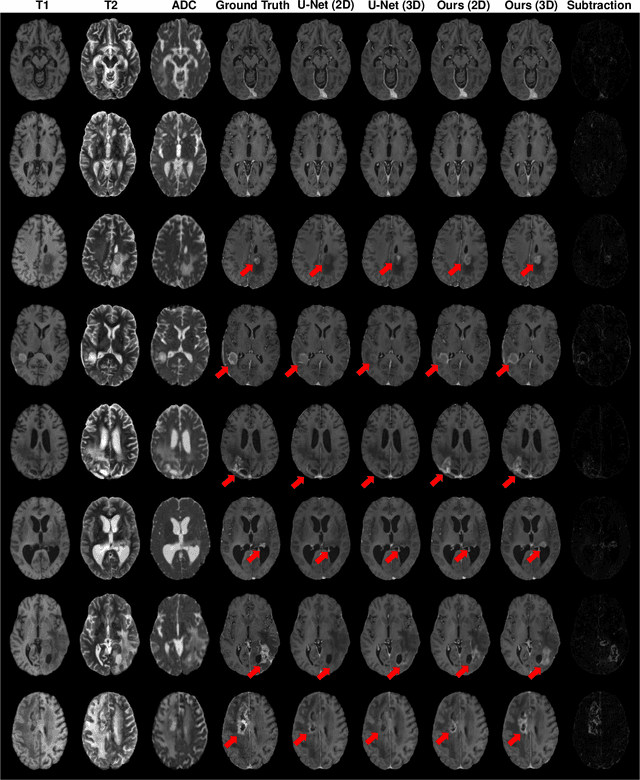

Abstract:Gadolinium-based contrast agents (GBCAs) have been widely used to better visualize disease in brain magnetic resonance imaging (MRI). However, gadolinium deposition within the brain and body has raised safety concerns about the use of GBCAs. Therefore, the development of novel approaches that can decrease or even eliminate GBCA exposure while providing similar contrast information would be of significant use clinically. For brain tumor patients, standard-of-care includes repeated MRI with gadolinium-based contrast for disease monitoring, increasing the risk of gadolinium deposition. In this work, we present a deep learning based approach for contrast-enhanced T1 synthesis on brain tumor patients. A 3D high-resolution fully convolutional network (FCN), which maintains high resolution information through processing and aggregates multi-scale information in parallel, is designed to map pre-contrast MRI sequences to contrast-enhanced MRI sequences. Specifically, three pre-contrast MRI sequences, T1, T2 and apparent diffusion coefficient map (ADC), are utilized as inputs and the post-contrast T1 sequences are utilized as target output. To alleviate the data imbalance problem between normal tissues and the tumor regions, we introduce a local loss to improve the contribution of the tumor regions, which leads to better enhancement results on tumors. Extensive quantitative and visual assessments are performed, with our proposed model achieving a PSNR of 28.24dB in the brain and 21.2dB in tumor regions. Our results suggests the potential of substituting GBCAs with synthetic contrast images generated via deep learning.